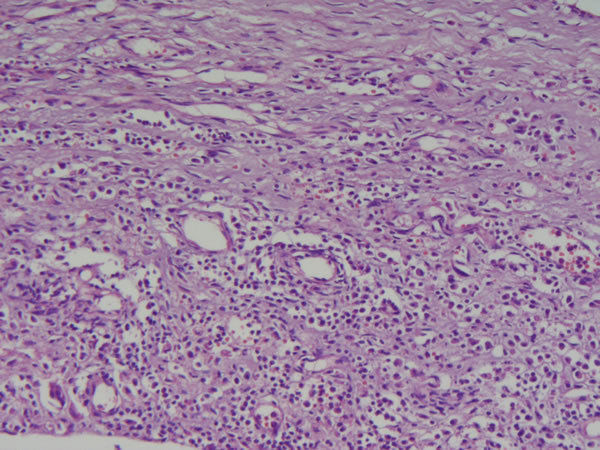

Pele - tec. pavimentoso estratificado, conj, e de granulação Reparo - fístula cutânea Outros achados: inflâmação crônica, inflamação aguda (apresenta área de solução de continuidade no centro) |

| Pele - tec. pavim. estratif., conj. e tecido de granulação Reparo - Fístula cutânea Causa: inf. bacteriana, Crohn | |

Pele - tec. pavim. estratif., conj. e tecido de granulação Reparo - Fístula cutânea Foco no tecido de granulação (novos vasos, muitas células de defesa) |